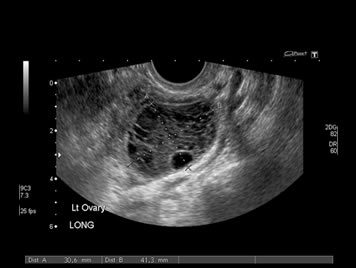

- Others, such as a pelvic ultrasound, may require a full bladder. You may need to drink up to six glasses of water two hours before the exam and not urinate until the exam is completed. So may start accumulate water at home before you move out.